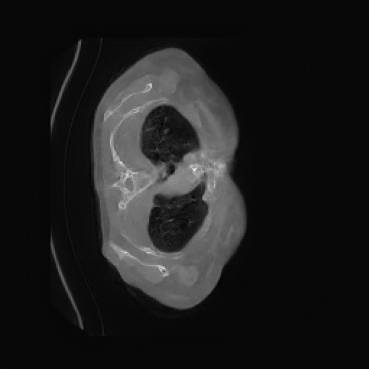

Appendix D More Generated Images Slices

![[Uncaptioned image]](x4.png)